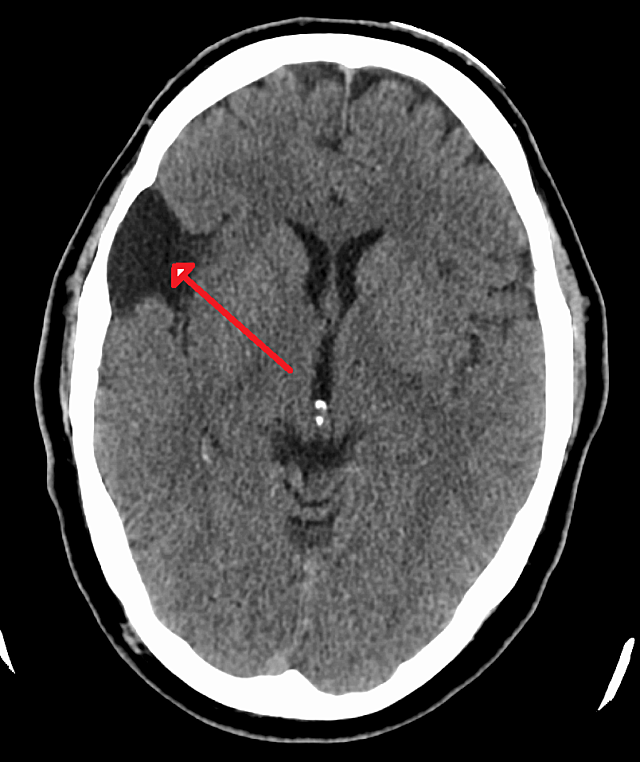

subarachnoid hemorrhage

best seen on CTH